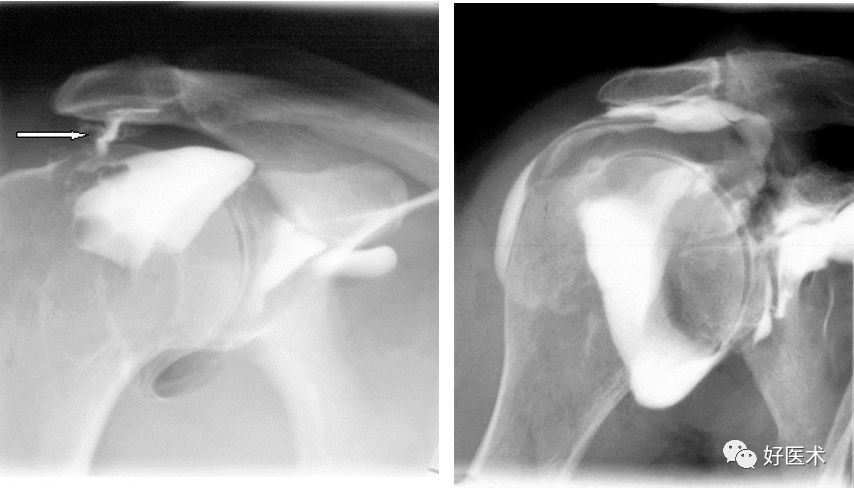

Bernageau位检查可对有肩关节不稳病史的受检者关节盂的前下段进行较好显像。Hill-Sachs病变可呈现于多个成像位置,包括顶斜位、前后位X线片等

肩关节顶斜位

对肱骨头的上后部分、肩关节关节盂前缘的下部很好的成像

准确评估骨性Bankart病变、Hill-sachs病变

后脱位:反Hill-Sachs损伤

后关节盂撕脱小骨折

Hill-Sachs损伤

Hill-Sachs损伤:肩关节前脱位时,肱骨头撞向关节盂缘可导致肱骨头的后外侧的嵌插骨折